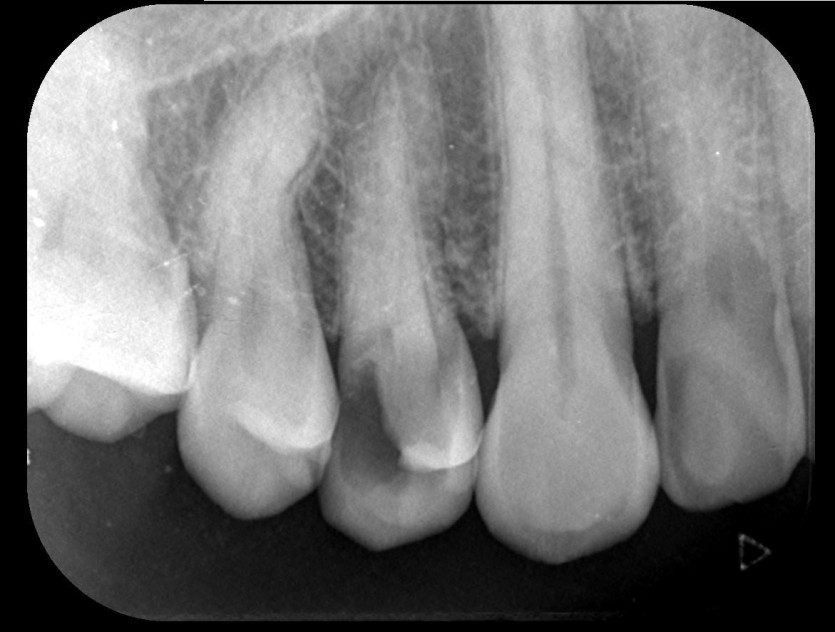

임플란트 사례